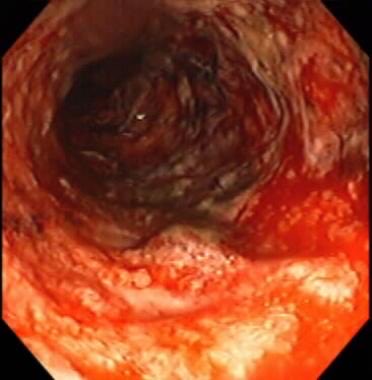

3️⃣ مناظير الجهاز الهضمي

✳️ المنظار السفلي للجهاز الهضمي او ما يعرف بمنظار القولون

ويعتبر أدق الفحوصات لتمكين الطبيب من معاينة الامعاء بشكل مباشر مع اخذ الخزعات وارسالها للفحص المجهري في المختبر